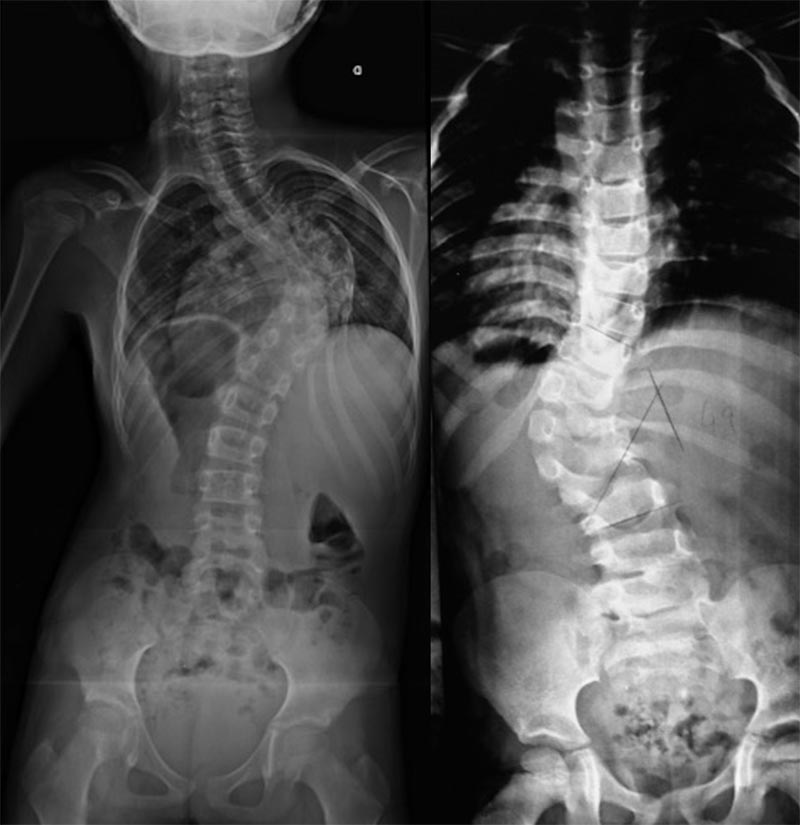

Radiografias são o principal método para o diagnóstico de escoliose congênita e suas mudanças evolutivas durante o seguimento1,6 (exemplo nas figuras 3 e 4). Sempre que possível, as radiografias devem ser feitas com o paciente de pé ou sentado devido a atuação da gravidade na possível acentuação da curva. A severidade das curvas é medida pelo ângulo de Cobb.

Figuras 3 e 4. Exemplos radiográficos demonstrando achados de escoliose congênita